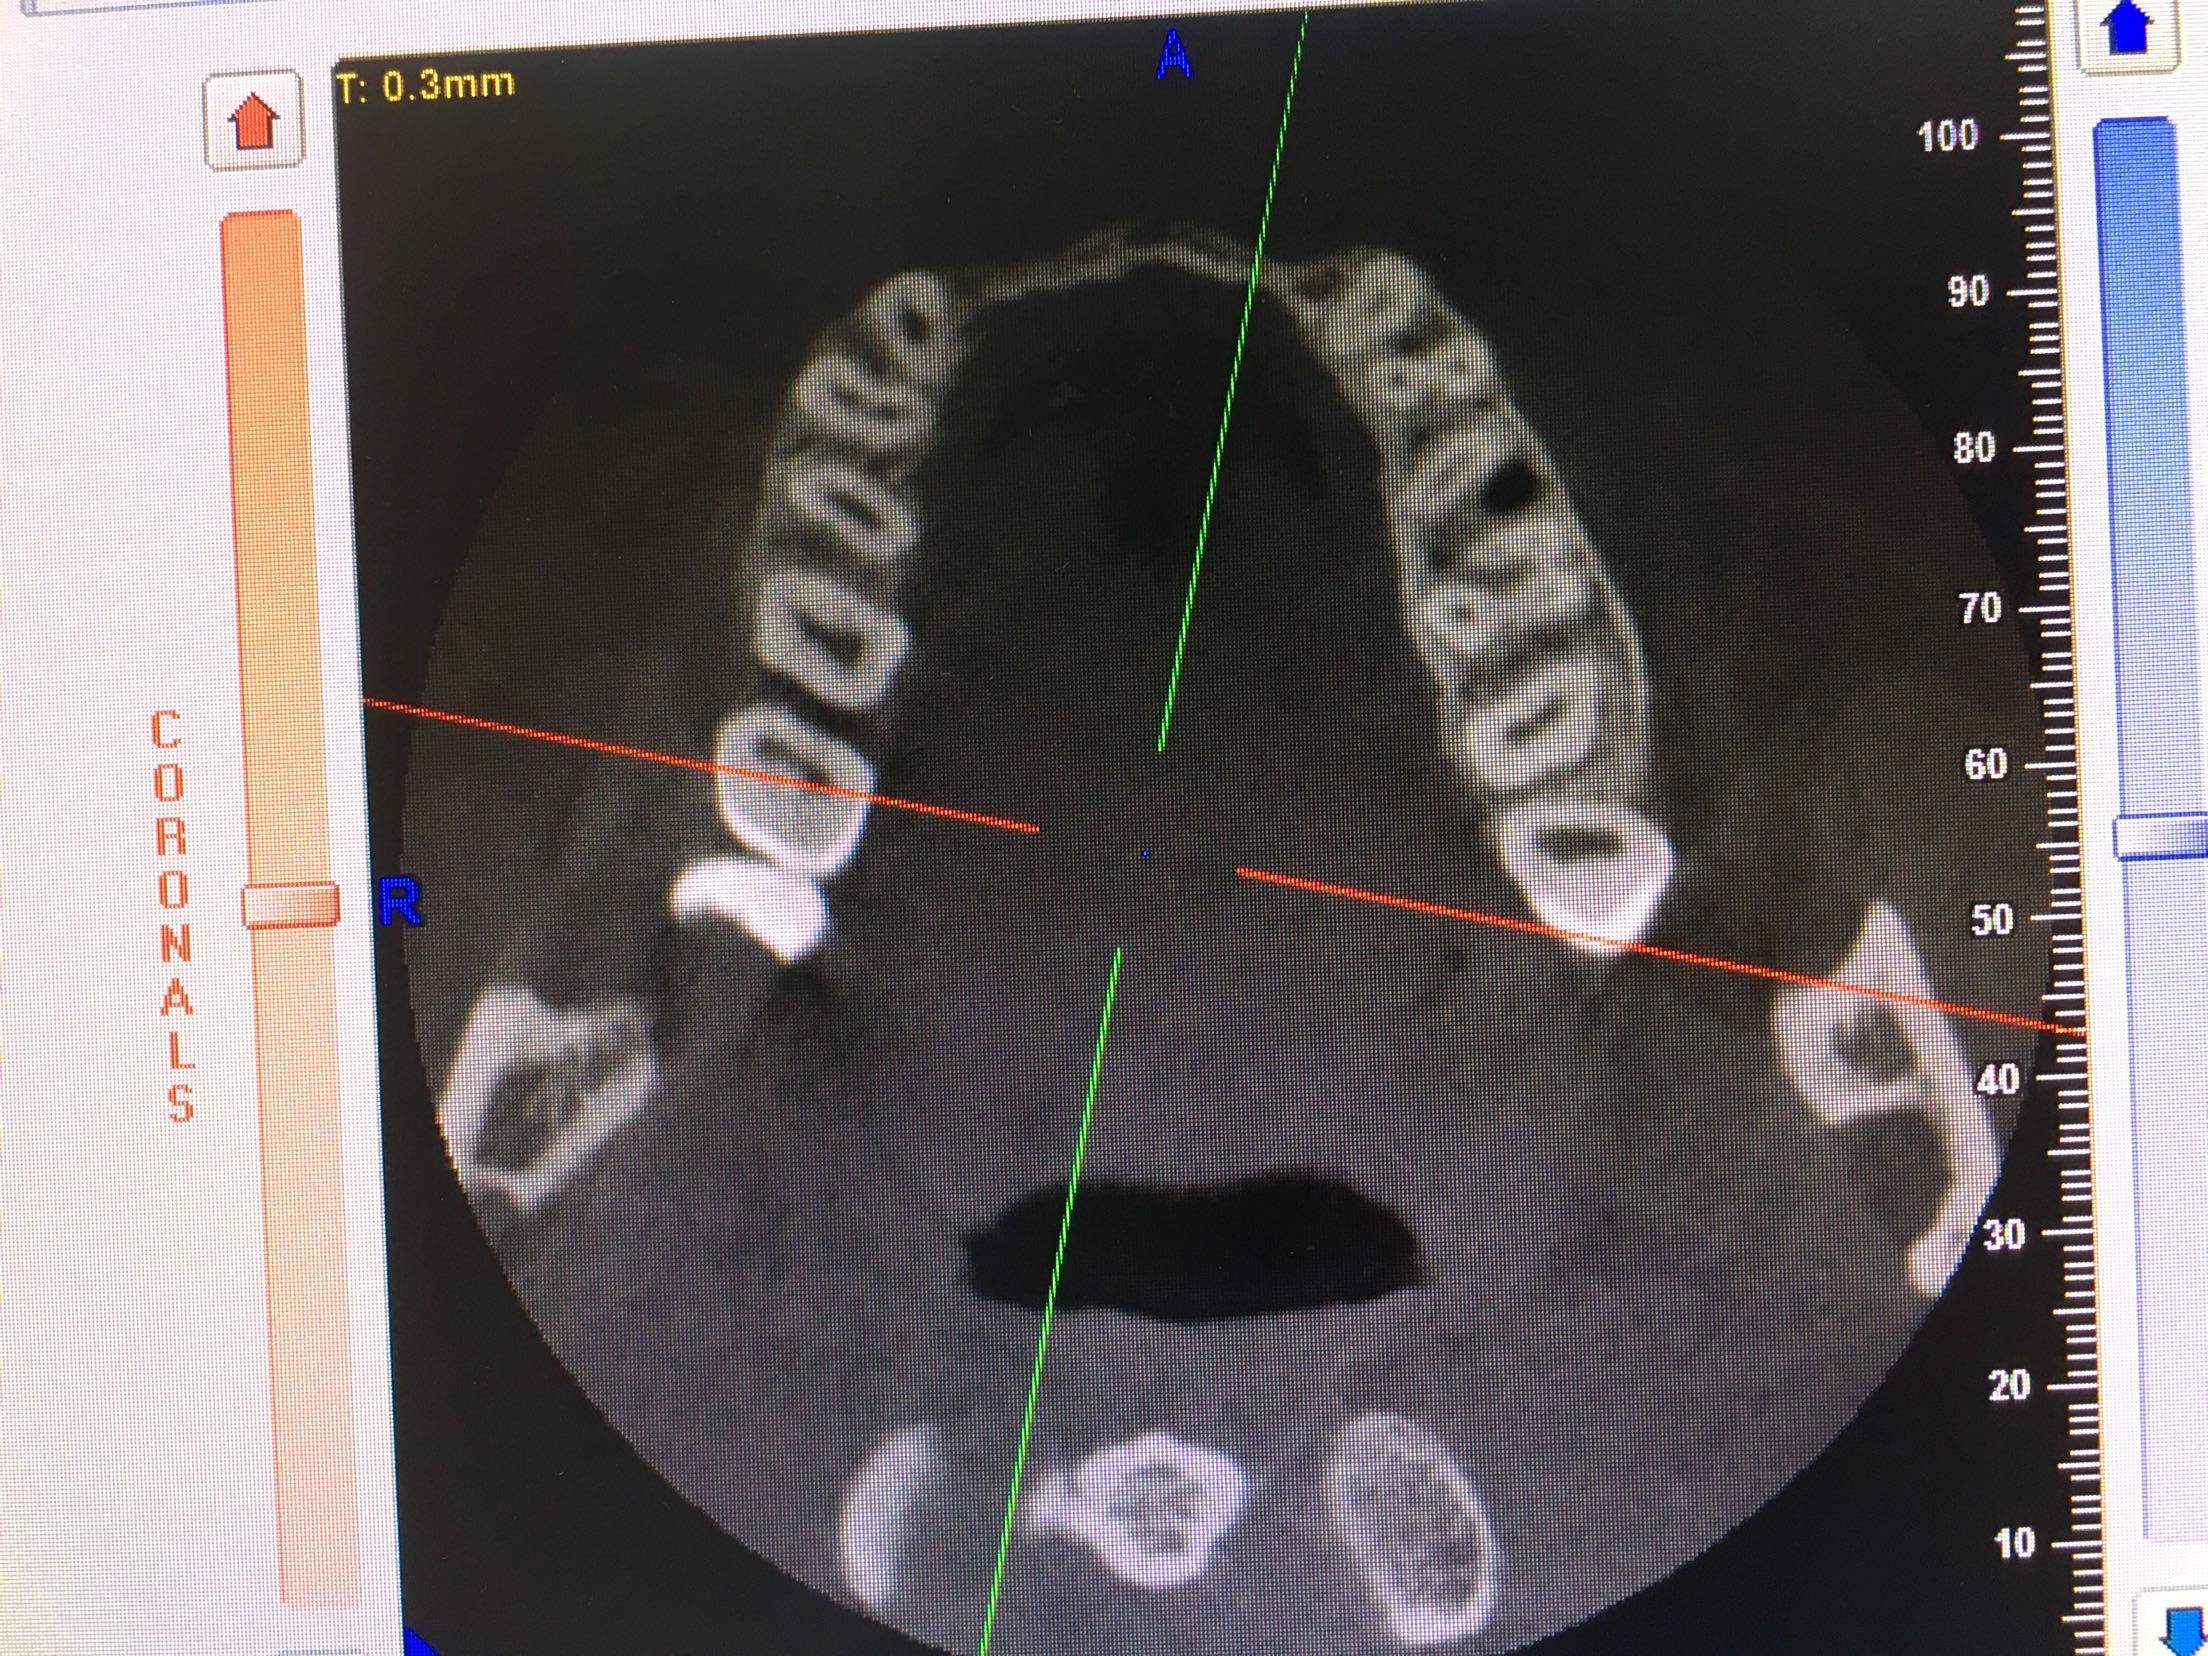

CBCT示11、12、21、22牙缺失,牙槽骨呈刀刃状,38、48牙阻生。

38、48牙超刀拔除,取双侧骨块,11、12、21、22梯形切口切开、翻瓣,切断粘骨膜松弛,骨块钛钉固定唇侧,植入Bio-ss骨粉0.5g,覆盖生物膜,严密缝合!嘱半年后种植!